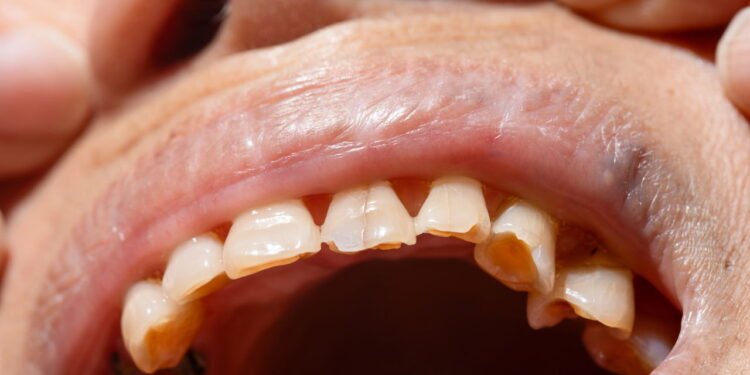

O Desgaste Dentário é um problema que afeta a saúde bucal de muitas pessoas, apresentando-se frequentemente através de sintomas como sensibilidade aumentada ao frio ou alimentos doces, superfícies dos dentes que se tornam achatadas ou ásperas e dores musculares na face ou ao mastigar. Esses sinais de alerta não devem ser ignorados, já que quando a estrutura natural dos dentes é perdida, eles se tornam mais vulneráveis a fraturas e outras complicações.

O hábito inconsciente de ranger ou apertar os dentes, conhecido como bruxismo, é uma das principais causas desse problema. O bruxismo pode ocorrer tanto durante o dia quanto à noite e resultar em dores de cabeça, incômodos nos ouvidos, além do desgaste significativo nos dentes e até problemas na articulação da mandíbula. Identificar o bruxismo é essencial para evitar complicações dentárias futuras.

A má oclusão dentária, ou seja, o desalinhamento entre os dentes superiores e inferiores, pode também contribuir para o desgaste dental. O contato desajustado entre os dentes ao fechar a boca sobrecarrega os dentes, gengivas e até a articulação mandibular, podendo trazer sérios danos.

Outro fator a considerar é a escovação dental inadequada. Pressão excessiva e uso de escovas de cerdas rígidas são prejudiciais e devem ser evitadas. O ideal é a utilização de escovas com cerdas macias, que permitam uma limpeza eficaz sem danificar o esmalte dentário. Além disso, condições de saúde como o refluxo gastroesofágico, que traz ácidos do estômago de volta à boca, podem causar erosão nos dentes.

Por fim, o envelhecimento natural também contribui para o desgaste do esmalte. Uma avaliação periódica com dentistas é recomendada para identificar e corrigir hábitos danosos. Técnicas modernas e minimamente invasivas ajudam a prevenir o agravamento desse problema, garantindo uma saúde bucal melhor e mais duradoura.